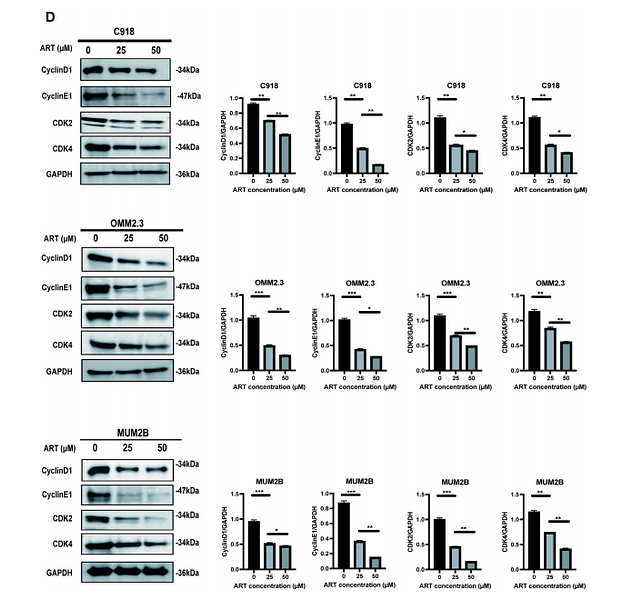

Integrating network pharmacology, molecular docking and experimental verification to reveal the mechanism of artesunate in inhibiting choroidal melanoma

Author: Ma Qing-yue, Liu Yi-chong, Zhang Qian, Yi Wen-dan, Sun Ying, Gao Xiao-di, Zhao Xin-tong, Wang Hao-wen, Lei Ke, Luo Wen-juan

PMID: 39185308

期刊: Frontiers In Pharmacology

应用: WB

反应种属: Human

发表时间: 2024 Aug

-